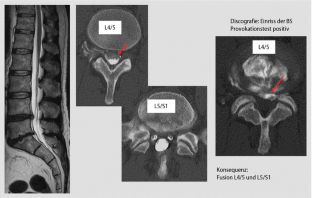

Abb. 2